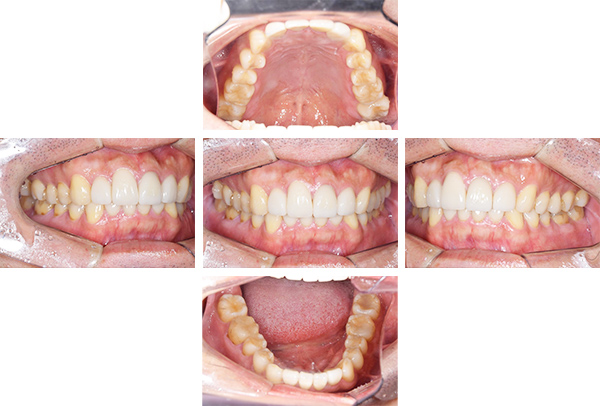

インレー症例

治療前

治療後

治療期間 8回(2ヶ月)

費用 ・セラミックインレー9本

合計:495,000円

治療リスク・副作用 ・詰め物、被せ物をする時は自分の歯を削ることになります

・歯ぎしり・食いしばりが強い方は、セラミックが割れてしまうことがあります。